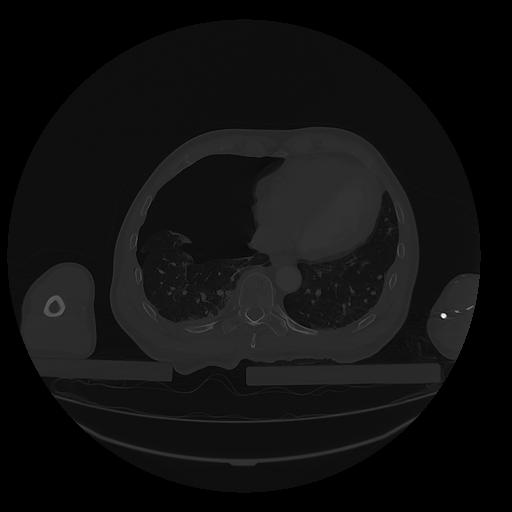

31 PULMON,CE,Vol,1.0,PULMON,,